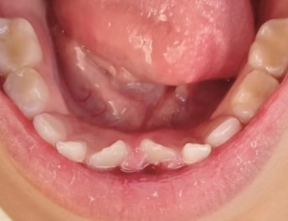

双排队形

现在很多孩子换牙的时候会出现“双排牙”:新牙和旧牙排成两排,同时出现在口腔里。这种情况叫做乳牙滞留,俗称“双排牙””,简单来说就是旧的乳牙还没来得及脱落,新的恒牙就已经迫不及待的长出来了。

图片

出现双排牙,提前拔除滞留的乳牙有利于新牙尽早的排齐,同时也便于清洁尤其是上颌的双排牙,应尽早拔除滞留乳牙,避免造成前牙反颌。因此,如果孩子出现了双排牙情况,是时候去拜访一下牙医了。